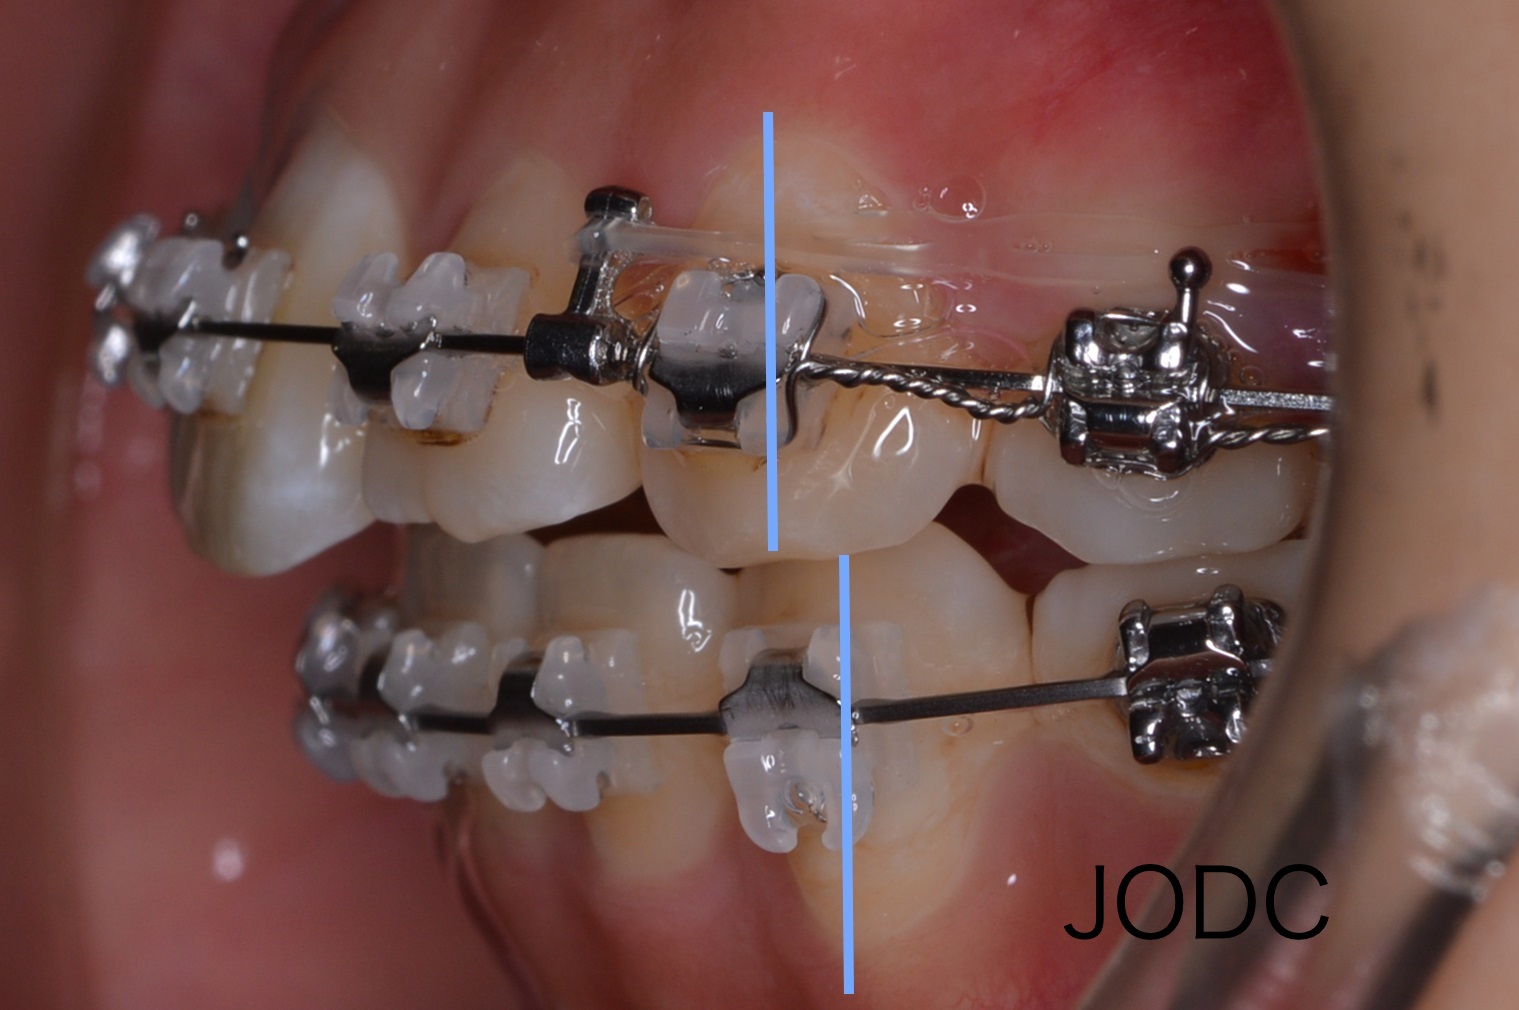

【3】TAD (矯正用インプラントアンカー)

矯正用インプラントアンカーと呼ばれる小さなネジのようなチタンスクリューを顎の骨に埋め込み、

アンカーを固定源とし大臼歯を遠心へ動かしていく治療です。インプラントアンカー1本埋入に要する時間は5〜10分程度で、矯正治療が終了したら口腔内から撤去します。通常のブラケットとワイヤーだけの矯正治療では、引っ張る力がワイヤーとつながった各々の歯にかかるので意図しない方向へ移動する事もあります。その点、矯正用インプラントアンカーを用いると歯を支点にする時と異なり、固定源が不動(移動する事がない)なので効率よく歯を動かす事が可能となります。

写真上が埋入時、写真下が3月後です。上顎犬歯を基準とし比較してみると全体的に遠心移動し上顎前突(出っ歯)も改善された事がよくわかります。上下顎の隙間が縮まりしっかりと咬めてますね。